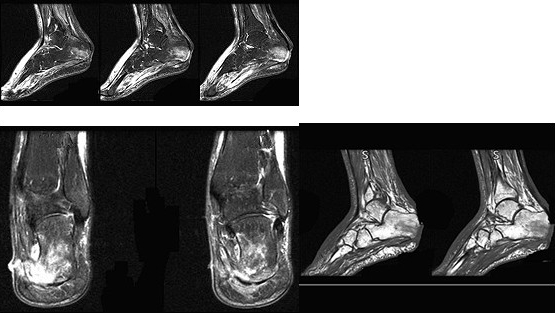

男,34岁,有糖尿病史,足跟部肿痛半年且有流脓,结合图像。最可能的诊断是()

A:未见异常

B:骨髓炎

C:结核

D:滑膜炎

E:类风湿关节炎